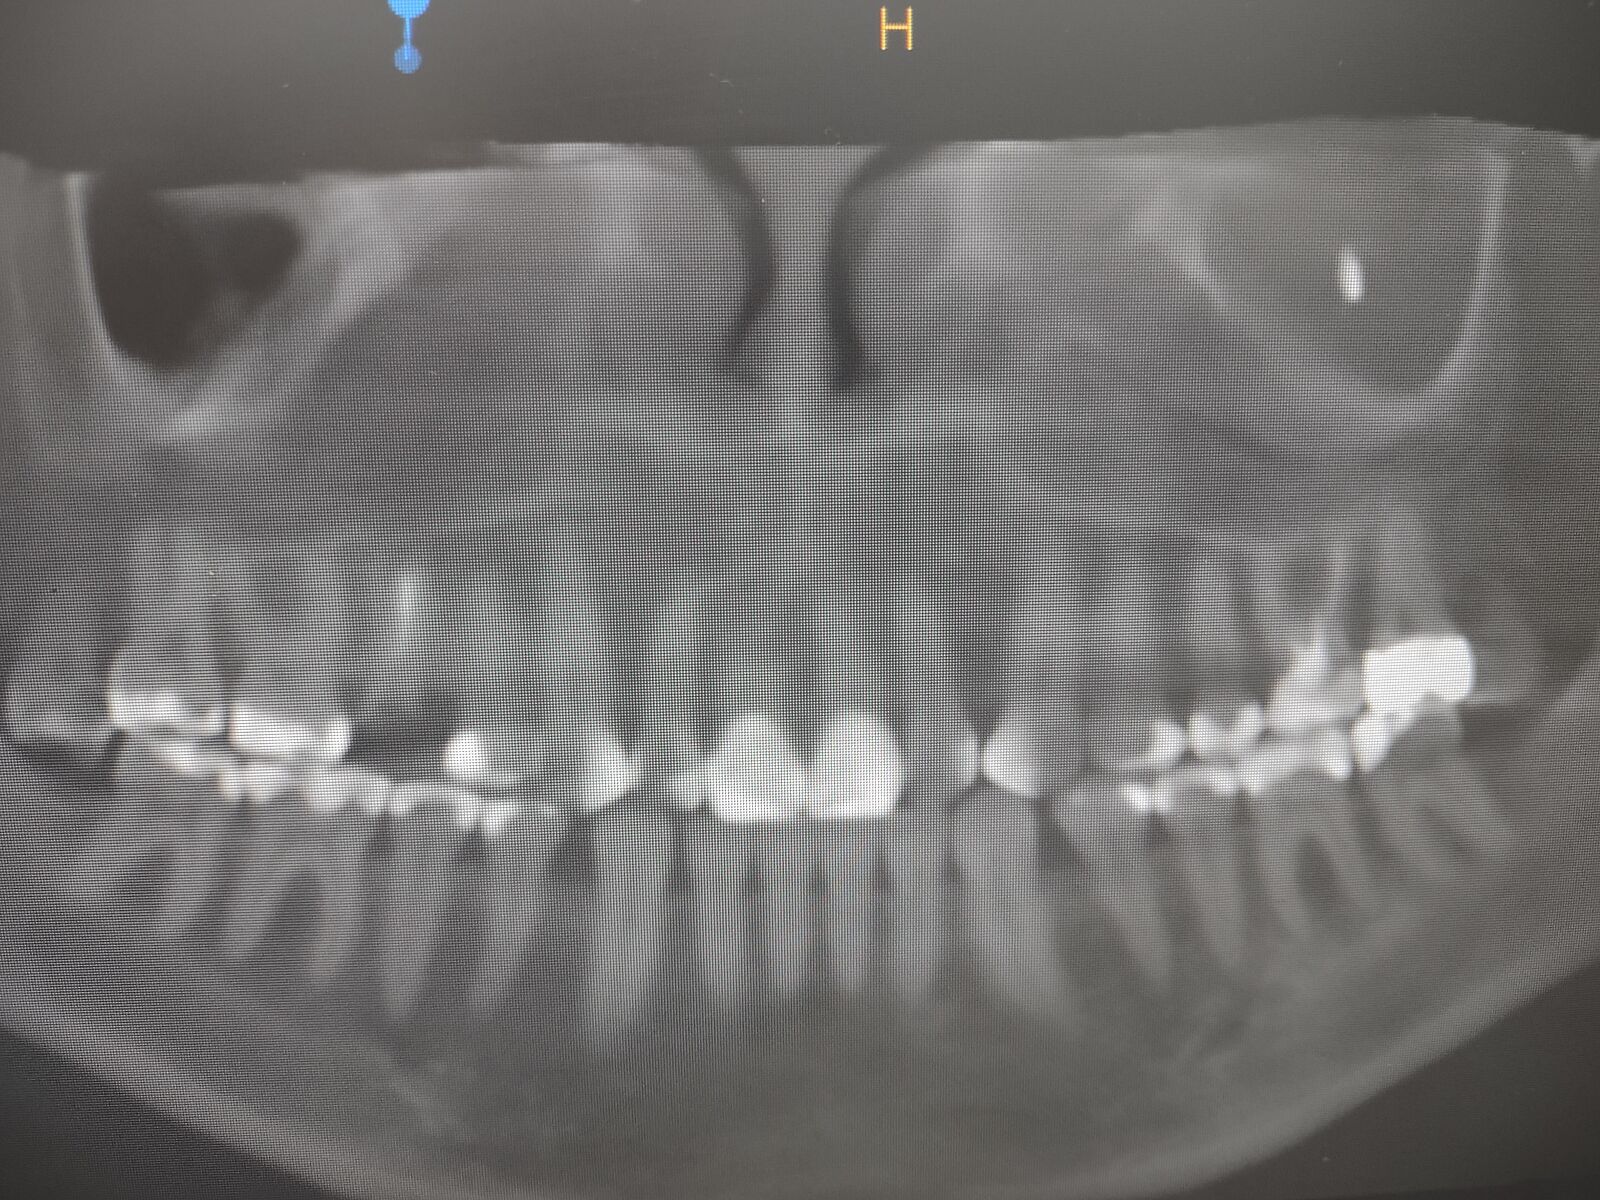

Что за проблема на снимке? Что-то серьезное?

Мне кажется гайморит , но я не лор. У вас пазуха чёрная, наполненная

Гайморит. На знімку якраз там, де світла маса. Чорне - то повітря, яке має бути в нормі, а тут пазуха заповнена. Треба лікуватися! Видужуйте!

А что это может быть за рисоподобное обраование?

Какое-то инородное тело в гайморовой полости. Из предполагаемого- пломбировочный материал, выведенный за верхушку корня при пломбировке каналов зуба. Зубы могут анатомически корнями выходить в гайморову. Хотя по этому снимку вроде далеко(

Я не врач, но у меня подобное было. Запломбировали зуб и материал попал в пазуху. КТ выглядело также. Была операция. Если предположат ’заодно выровнять перегородку’ - трижды подумайте!